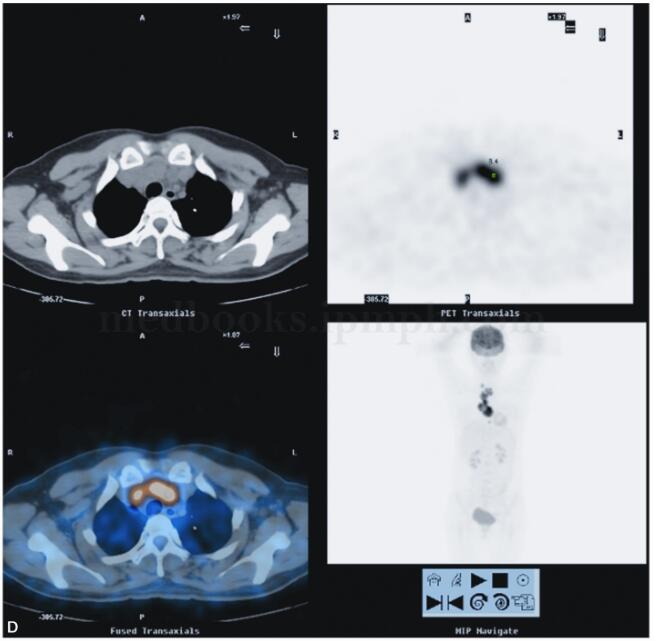

2010年5月10日于我院18F-FDG PET/CT检查:纵隔内及右肺上叶前段病变,代谢异常升高,考虑慢性感染性疾病可能性大(结核肉芽肿?),请结合临床,进一步完善结核相关检查,必要时纵隔镜活检以除外恶性病变(图2)。

图2 PET/CT示右肺上叶前段纵隔旁见高密度实变影,内见充气支气管影,FDG代谢放射性分布异常浓聚(SUVmax=12.4)。前纵隔内见软组织密度肿块影,最大截面积约为5.2cm×3.0cm,其内密度不均,见低密度坏死区,实质区FDG代谢放射性分布异常浓聚(SUVmax=15.0),邻近心包;右锁骨上、前上纵隔、主肺动脉窗,气管叉下(其内见钙化灶)及心包右旁见肿大淋巴结影,部分融合趋势,FDG代谢放射性分布异常浓聚